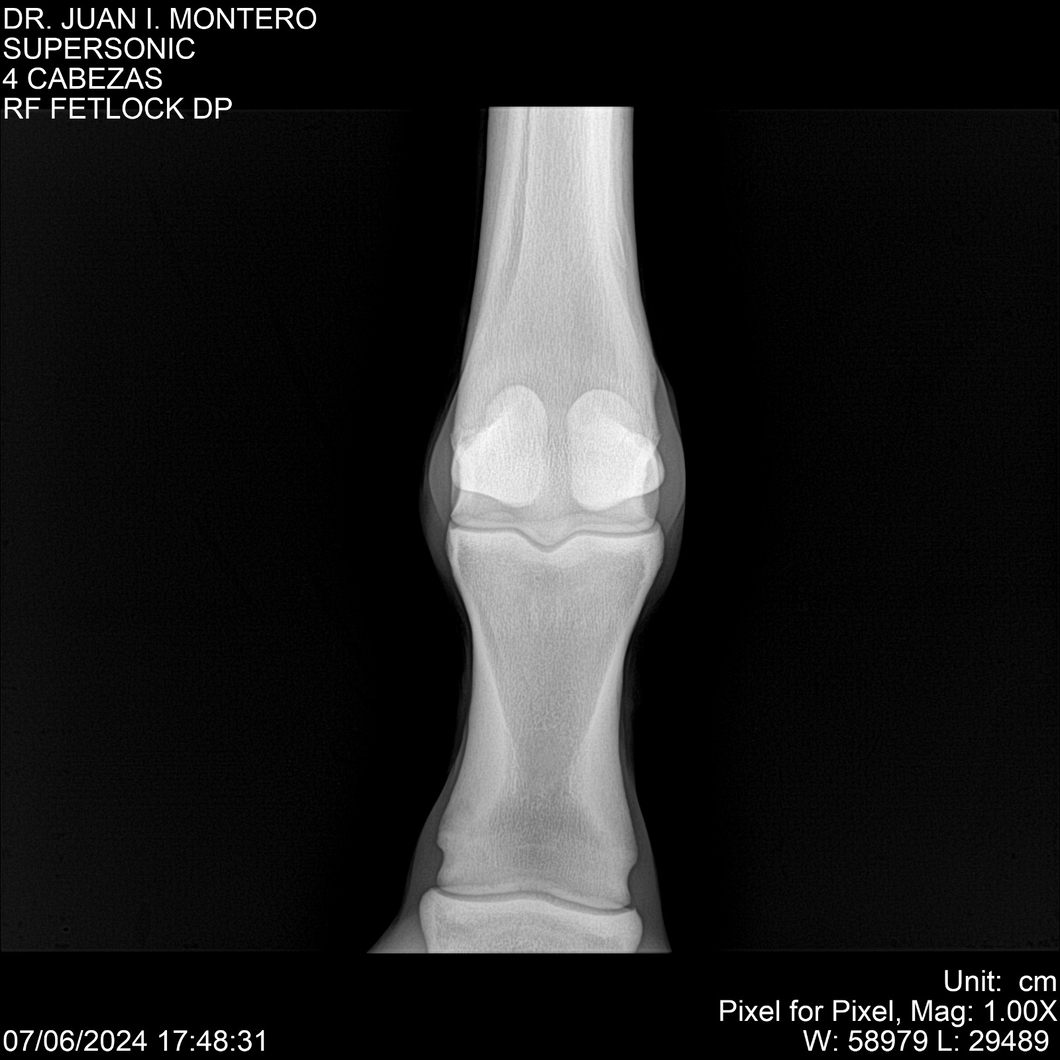

LOTE 5, SUPER SONIC Lote Anterior Volver al remate Lote Siguiente Ficha Contacto Montevideo - Ficha del Lote Identificador: #281089 Categoría: Yeguarizos Montevideo - 69 Visualizaciones ClicData Contacto Empresa: Abelenda N. R., Walter Hugo Nombre*: Teléfono* : E-mail* : Mensaje Enviar Registrese gratis Este contenido Exclusivo está disponible sólo para usuarios registrados Ingresar